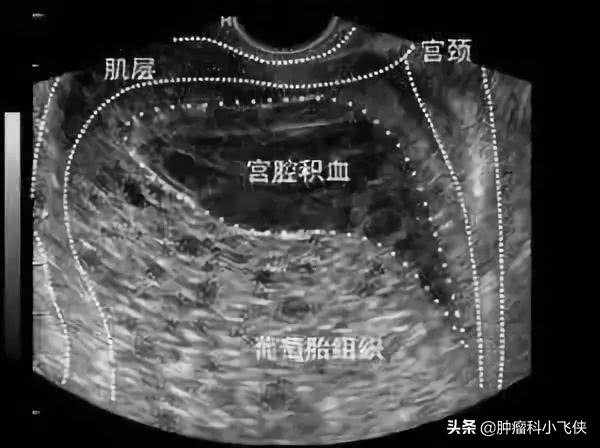

超声是诊断葡萄胎的重要手段之一,超声下见子宫明显大于孕周,但没有妊娠囊或胎心搏动,宫腔内充满无数小的低回声或者无回声区, 形如雪花,又名落雪征。部分性葡萄胎可见由水泡状胎块所引起的超声改变及胎儿或羊膜腔,胎儿常合并畸形。